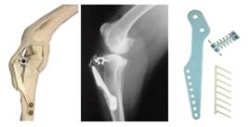

The TTA procedure developed by Tepic and Montavon is designed to bring the tibial plateau to sit at 90 degrees to the straight patella ligament. This effectively neutralizes the shear forces within the stifle, under loading, making the stifle stable.

This is achieved by advancing the tibial tubercle and stabilizing the created defect using a titanium cage and plate. The cage is selected for both thickness and width.

The implants are secured using titanium screws. Titanium is very osteoconductive resulting in rapid healing. The use of stainless steel implants is not recommended.

TTA image